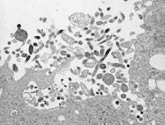

図.ニパウイルスの電子顕微鏡像(長崎大学熱帯医学研究所森田公一氏提供)

マラヤ大学では、第3のクラスターの初期に死亡した3例より得られた髄液のうち、2例についてウイルス分離を試みたところ、Vero細胞に接種したものについて接種5日目に合胞体形成が確認された。形態的にはパラミクソウイルス様であったが、同定不能であった。既知のウイルスおよびJEウイルスについてはことごとく陰性であった。このウイルスは、米国CDC(Centers for Disease Control and Prevention)によって、1994年にオーストラリアにおいて発見されたパラミクソウイルスの新種であるHendra virus(付2参照:当初equine morbilivirusと呼ばれていた)と類似のウイルスであることが判明した。

しかしこのウイルスは遺伝子レベルではHendra virusとは21%、同じくアミノ酸レベルでは11%の変異が見られ、近縁であるが独立の新パラミクソウイルスであると考えられた。当初Hendra virus-like virusと呼ばれていたこのウイルスは、ウイルスが分離された患者の村と川の名前にちなんで、新たにNipah virus(ニパウイルス)と名付けられた(図)。